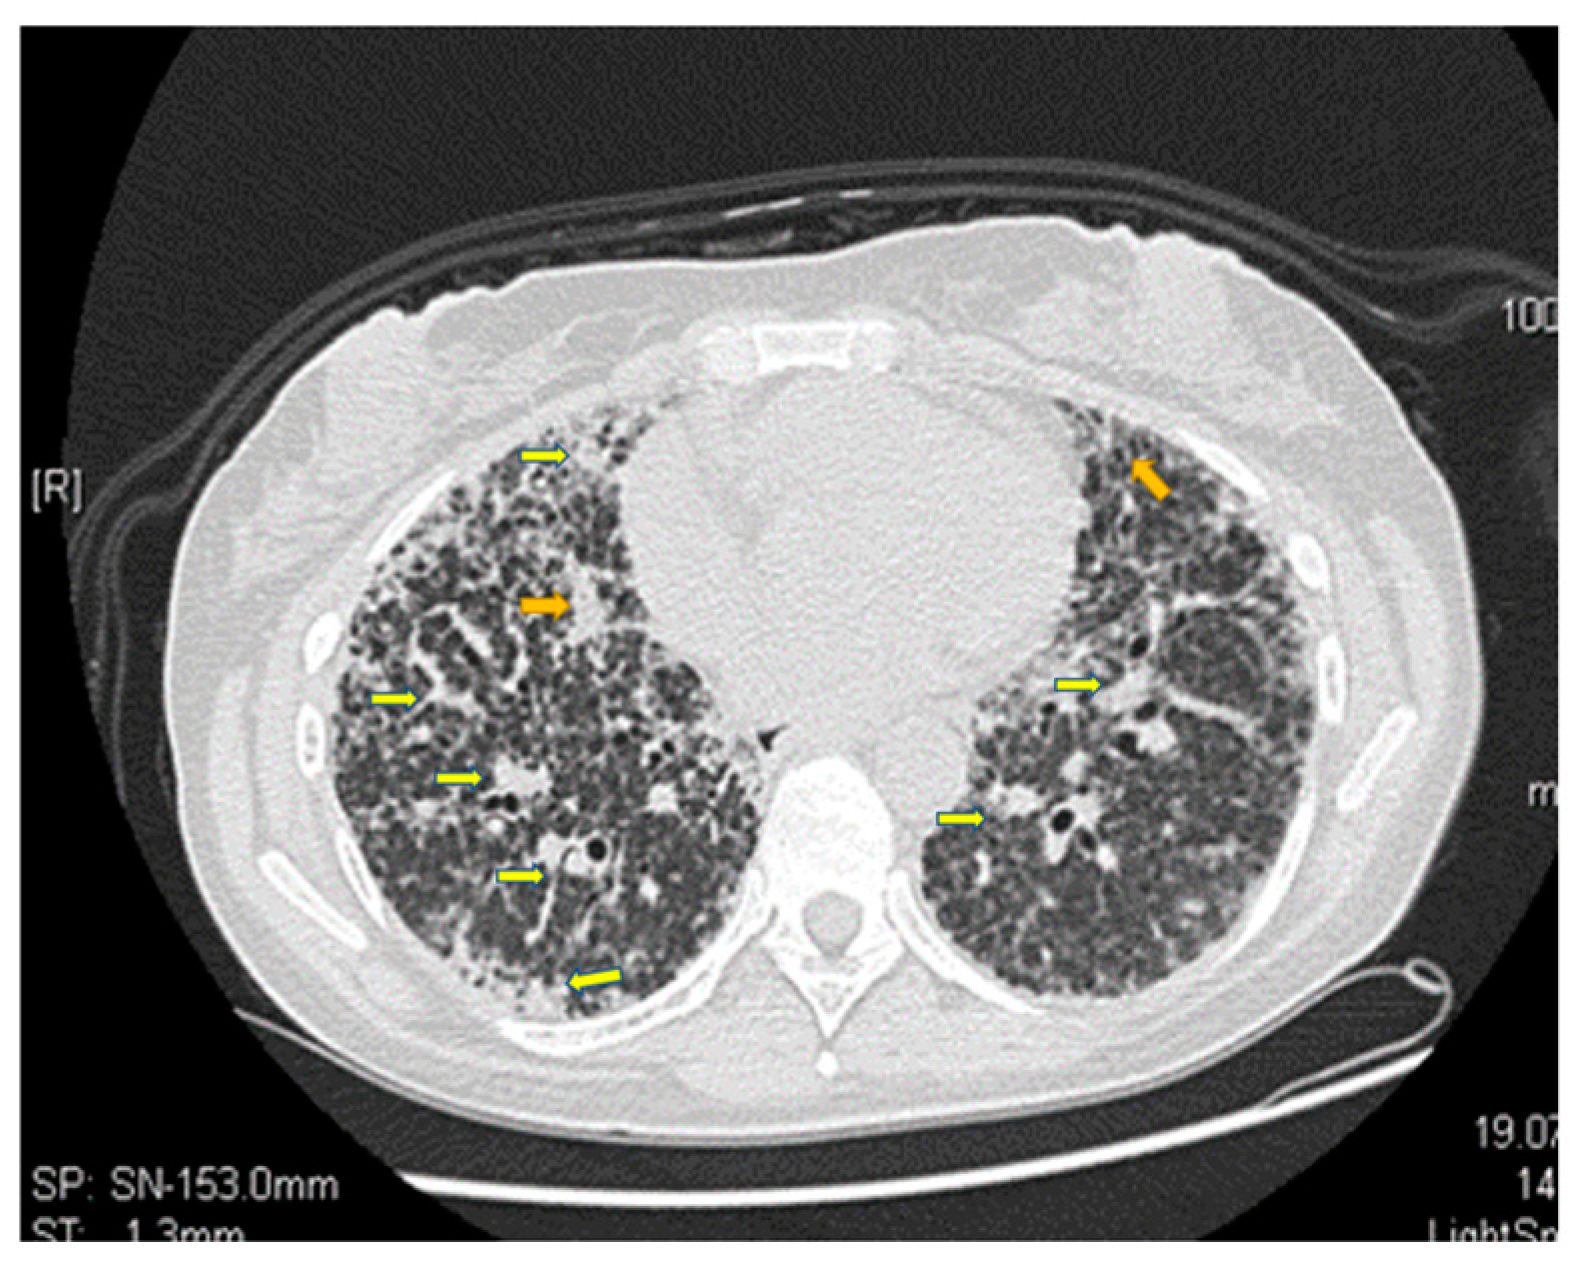

- Gupta, N.; Finlay, G.A.; Kotloff, R.M.; Strange, C.; Wilson, K.C.; Young, L.R.; Taveira-DaSilva, A.M.; Johnson, S.R.; Cottin, V.; Sahn, S.A.; et al. Lymphangioleiomyomatosis Diagnosis and Management: High-Resolution Chest Computed Tomography, Transbronchial Lung Biopsy, and Pleural Disease Management. An Official American Thoracic Society/Japanese Respiratory Society Clinical Practice Guideline. Am. J. Respir. Crit. Care Med. 2017, 196, 1337–1348. [Google Scholar] [CrossRef] [PubMed]